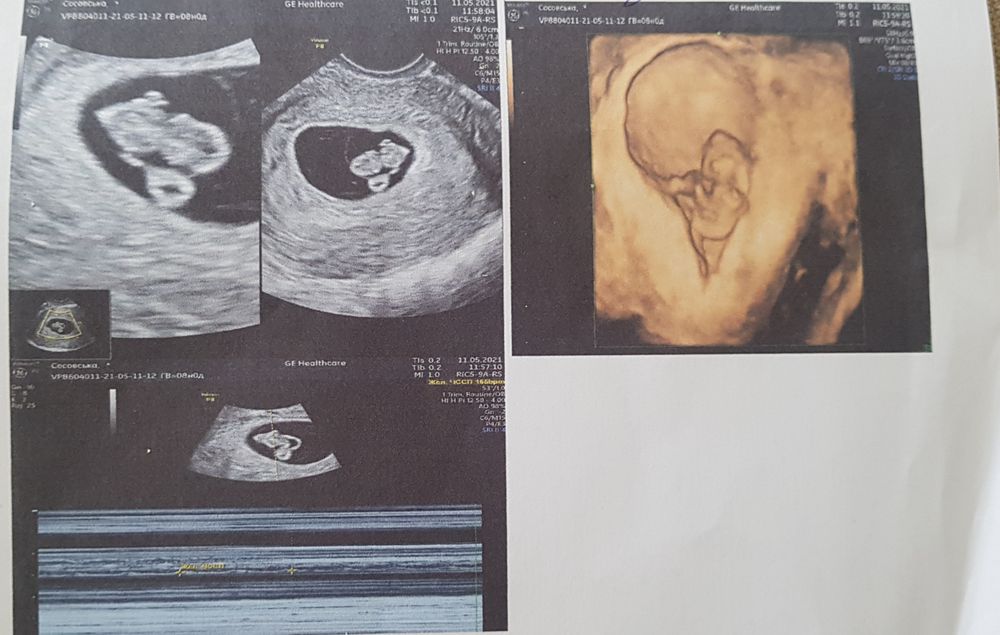

УЗИ делала вагинально оба раза. Первое фото 6 недель по М, а второе 8 недель по М. Итак, у кого какие предложения?!😅😅

вот эта белая часть вроде как хорион, он и прикрепление эмбриона по левой стороне. А при трансвагинальном узи слева это мальчик